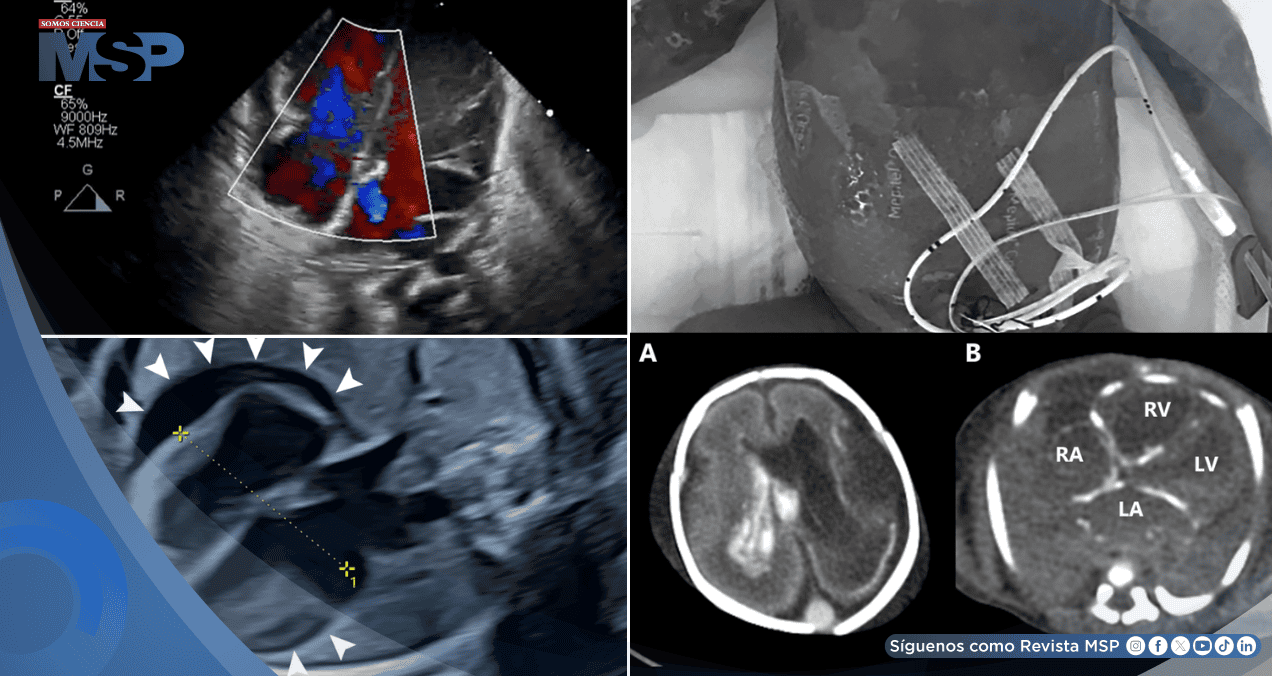

Los estudios revelaron bradicardia sinusal persistente de 100 latidos por minuto, acompañada de un derrame pericárdico circunferencial de 7-8 milímetros de ancho. Estos hallazgos se completaron con la aparición progresiva de dilatación del ventrículo derecho y múltiples lesiones hiperecoicas en el parénquima hepático, configurando un cuadro de afectación multisistémica de origen indeterminado.

Los estudios complementarios revelaron anemia severa, trombocitopenia marcada y coagulopatía grave, mientras la ecocardiografía demostró insuficiencia mitral y tricuspídea severa. Ante la sospecha fundada de infección herpética congénita por las lesiones cutáneas características, se inició tratamiento empírico con aciclovir.

La tomografía computarizada post mortem reveló hallazgos compatibles con infección congénita diseminada, incluyendo dilatación ventricular derecha, hemorragia intracraneal y calcificaciones en pared cardíaca, hígado y glándulas suprarrenales. Cabe destacar que la madre resultó asintomática pero con serología positiva para infección reciente por VHS, evidenciando la posibilidad de transmisión vertical sin sintomatología materna aparente.